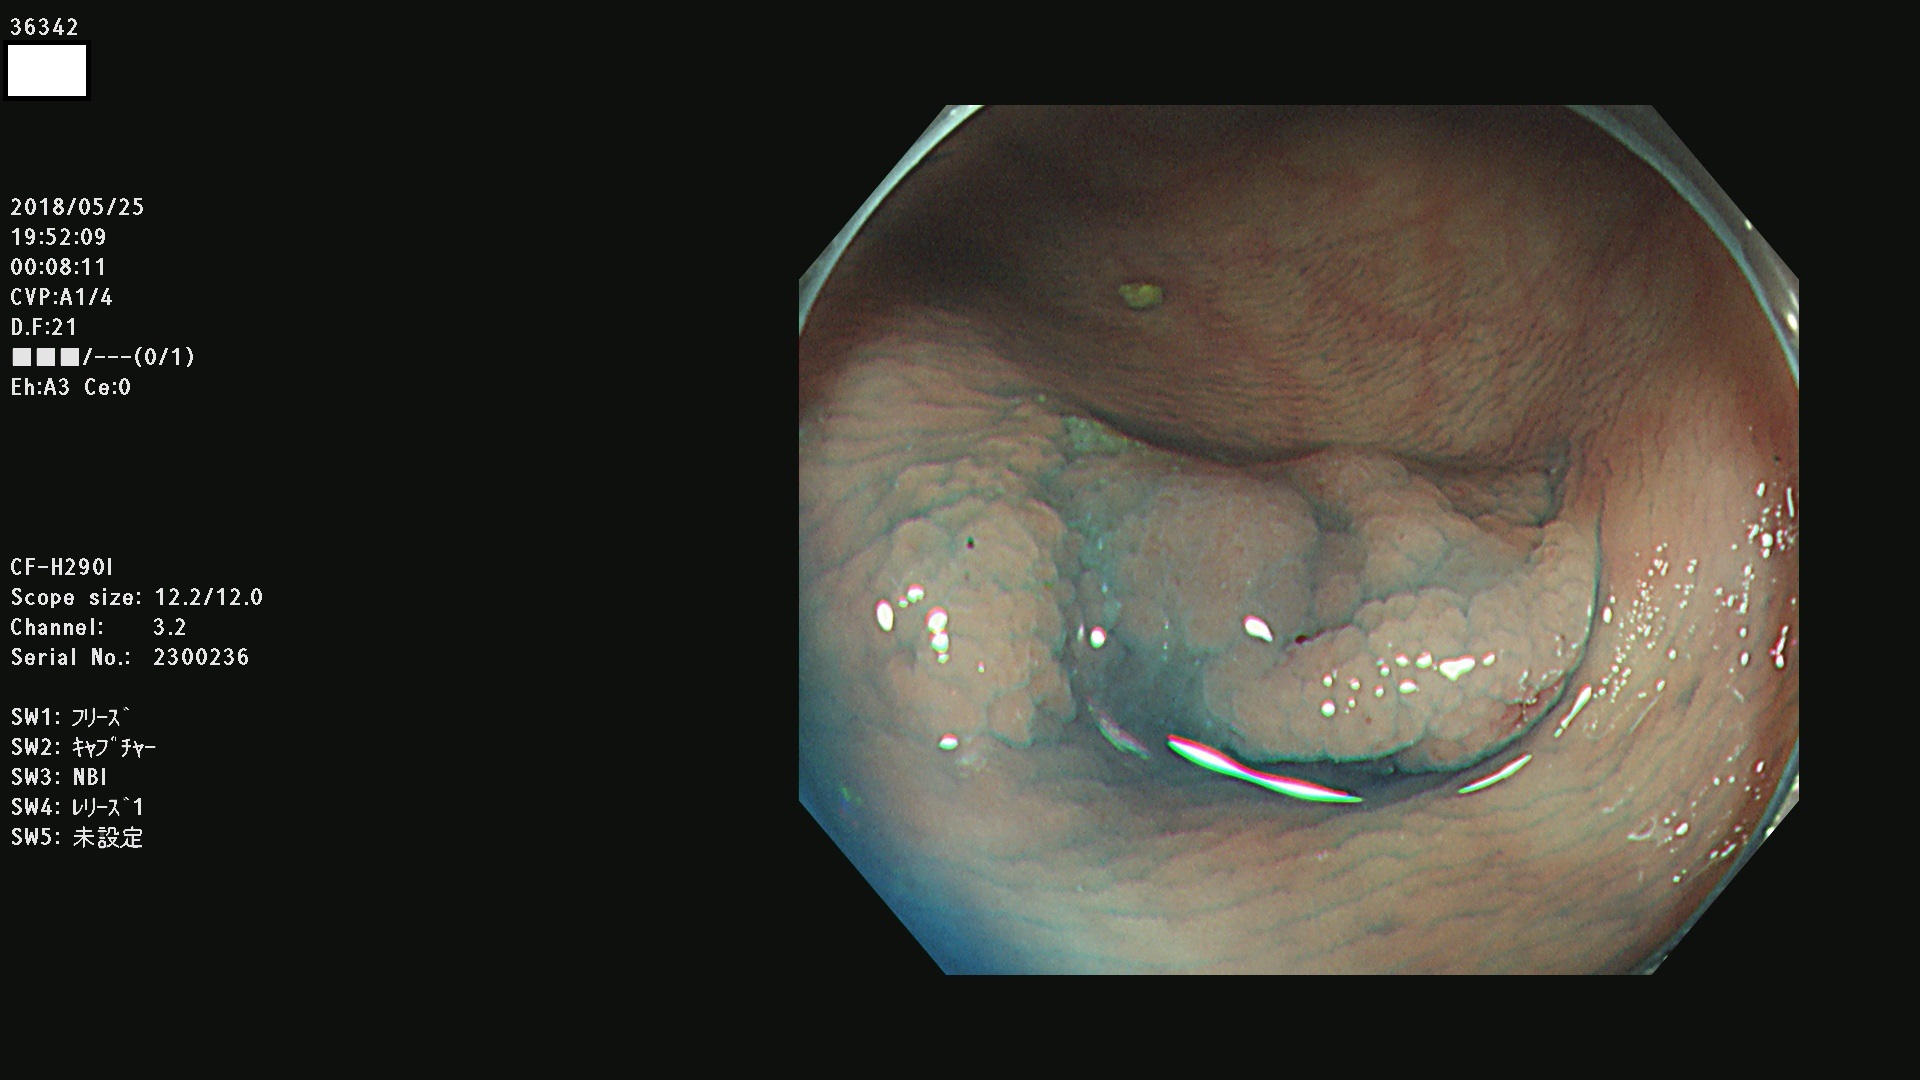

腺腫発見率 68 % (カルテ番号 36300〜36399の100名の方の検査結果で集計)大腸癌検診最新情報

以下のカルテ番号の方に腺腫(Adenoma,Group3〜5)が見つかりました(集計法)

36300 36302 36305 36306 36307 36308 36310 36311 36312 36313 36314 36315 36316 36318 36321 36322 36324 36325 36326 36327 36330 36332 36333 36334 36335(SSAPのみ) 36337 36338 36339(SSAPのみ) 36340 36341 36342(SSAPのみ) 36343 36344 36346 36348 36349 36351 36353 36354 36355(SSAPのみ) 36356 36357 36358 36359 36364 36365 36366 36367 36370 36374 36376 36379 36381 36382 36383 36384 36385 36387 36388 36389 36390 36392 36393 36395 36396 36398 36399

発見困難で危険性の高い平坦型病変(上記100名より抽出) ![]()